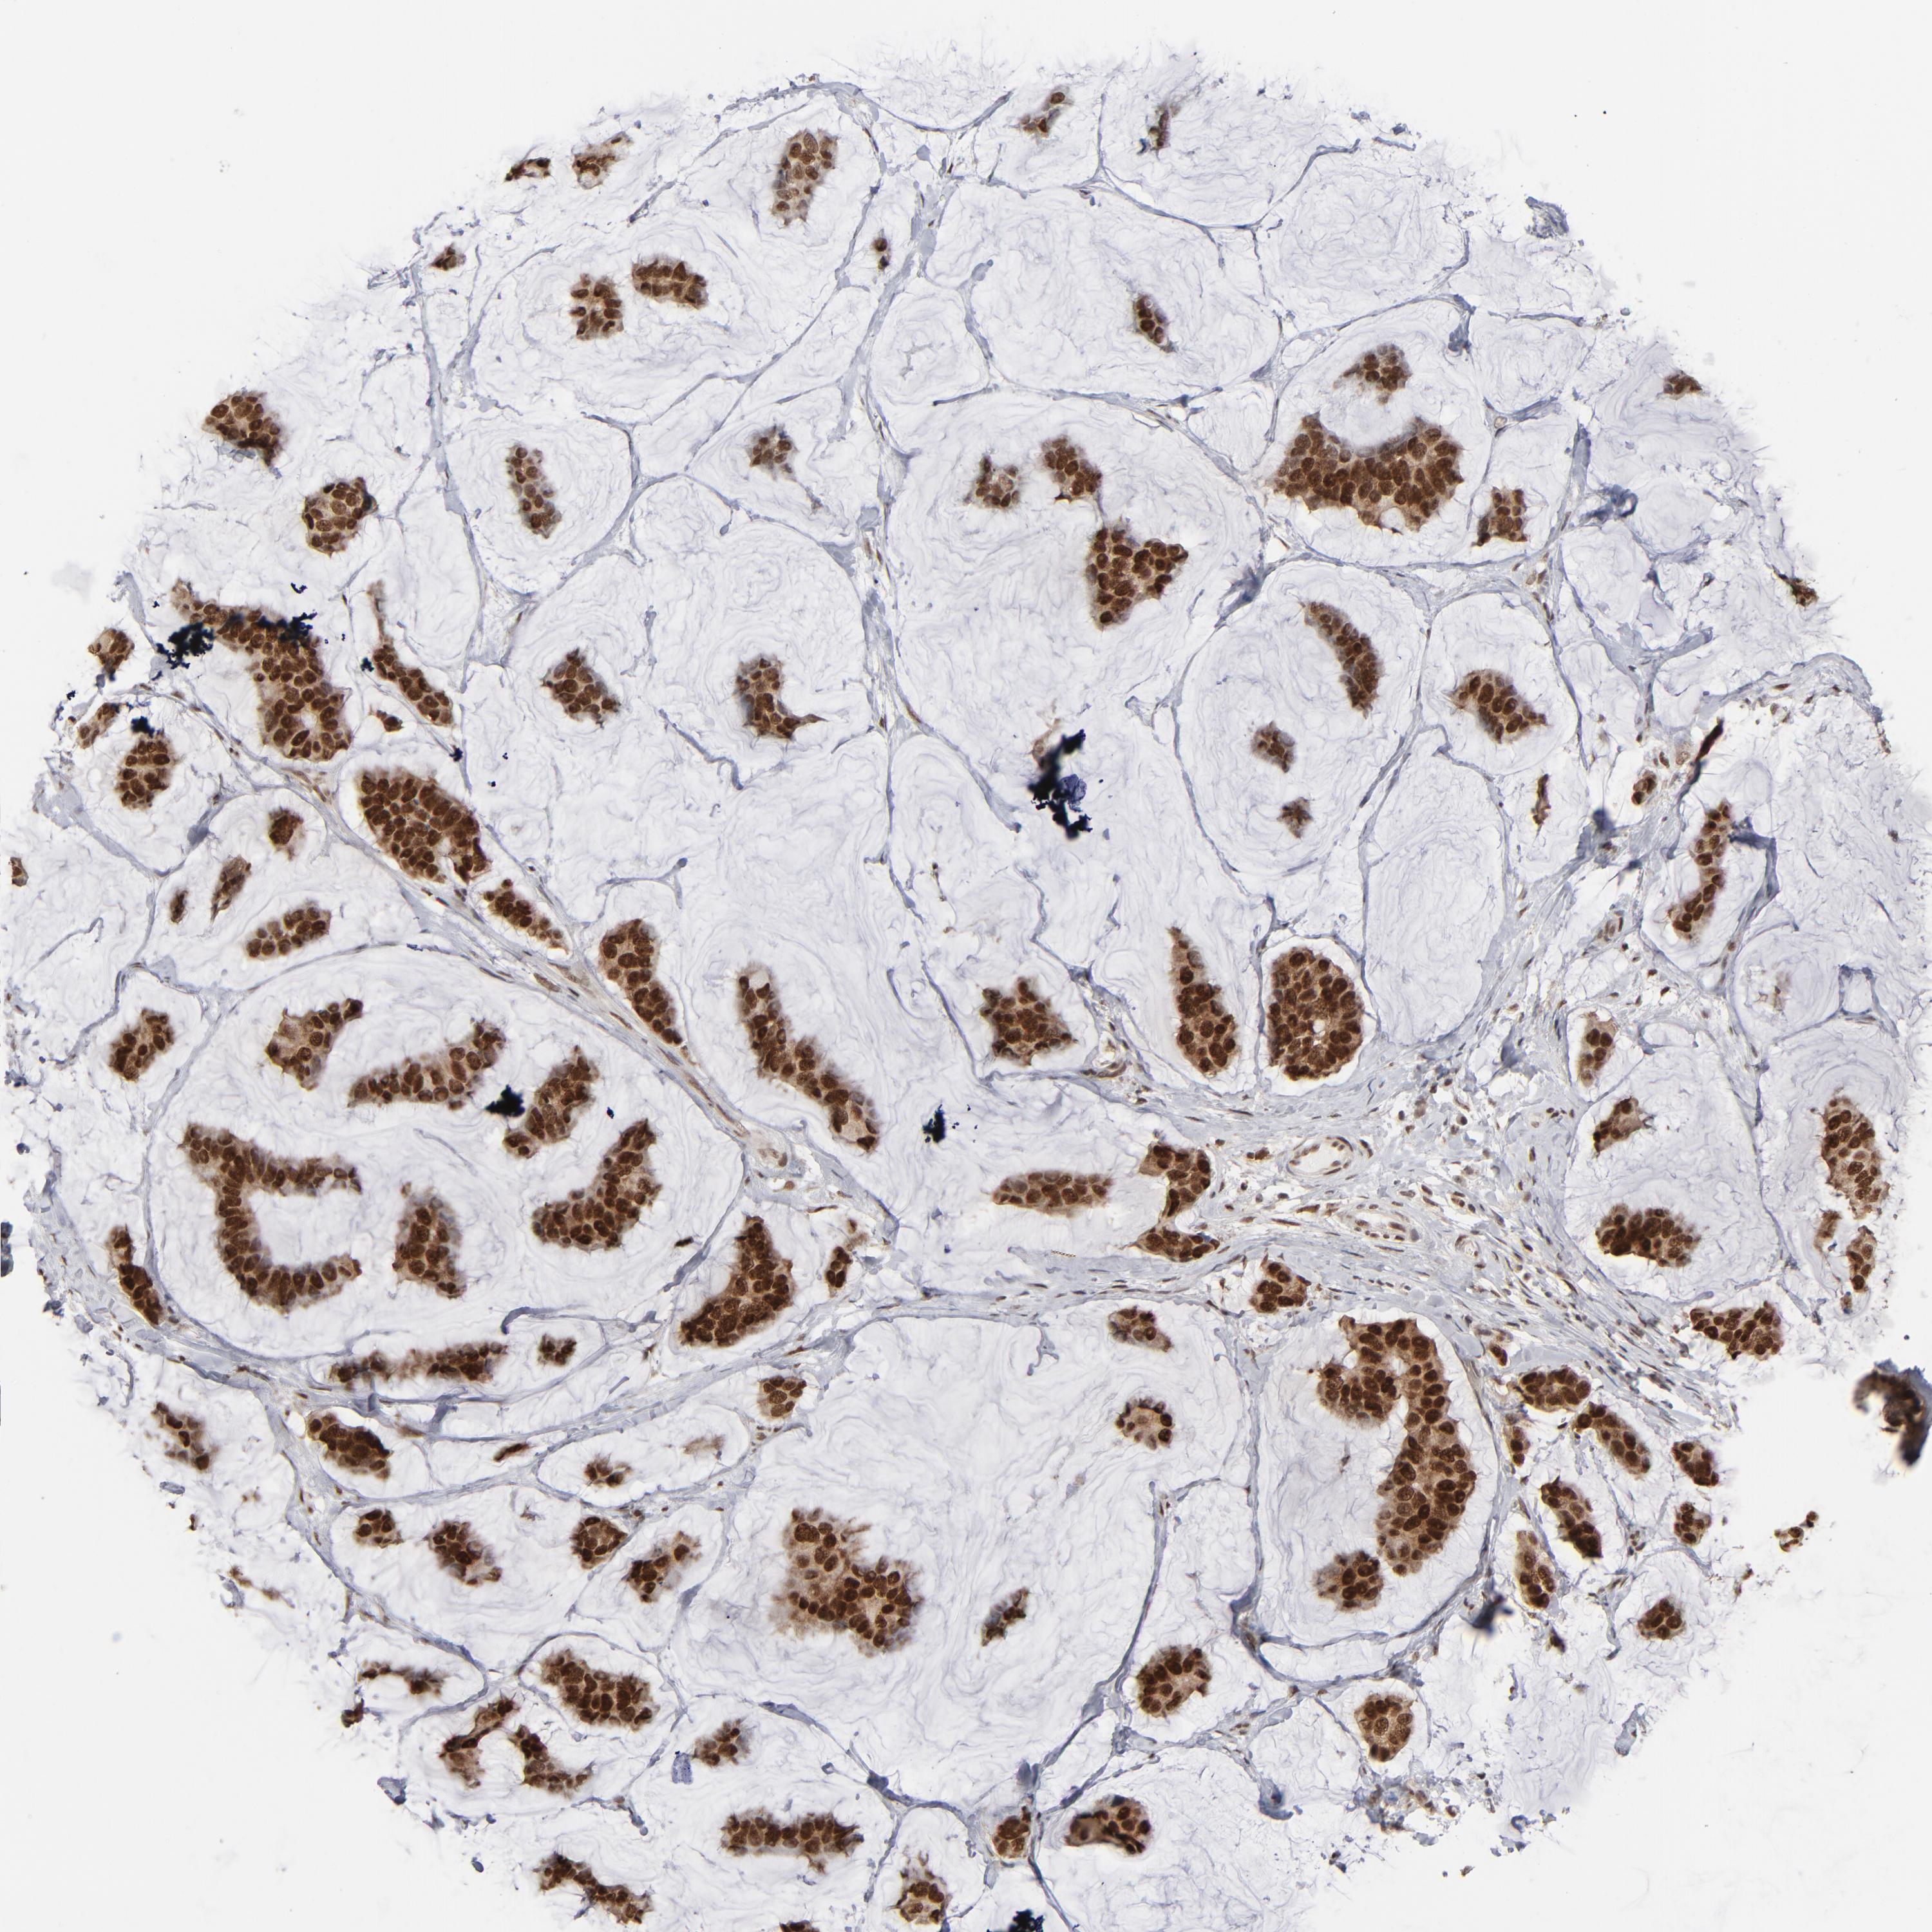

CANCER BREAST CANCER Show tissue menu

BRCA TCGA BRCA VALIDATION PROTEIN EXPRESSION